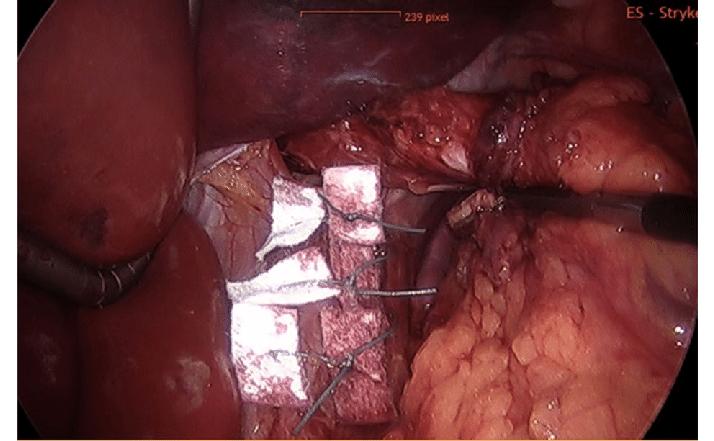

Here, we see pledgeted sutures for partial resection of the spleen, and for plication of the diaphragm.

Pledgets seem to be popular in foregut surgery for a variety of different cases. I assume the tissue there is fragile (I don't do foregut; for those that like it, bless you).